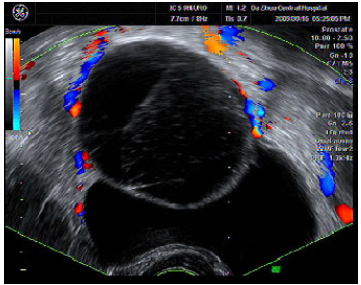

超声介入治疗卵巢囊肿36例